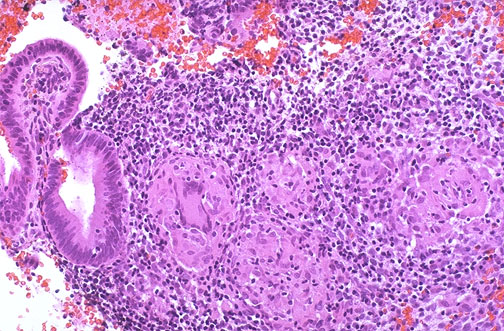

| Chronic endometritis can occur in patients with chronic pelvic inflammatory disease, as a postpartum or postabortion complication, in association with intrauterine devices (IUD's), or with tuberculosis. In a sixth of patients there is no definable cause for chronic endometritis. The granulomatous form of chronic endometritis shown here is due to drainage of tuberculous salpingitis into endometrial cavity. This occurred in a patient with disseminated tuberculosis. |